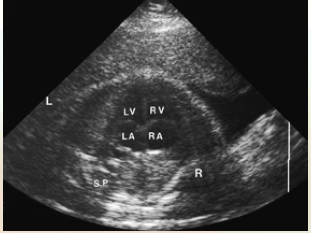

Fetal heart lies more horizontal than the neonatal heart because the lungs are not inflated in utero

This allows for image planes not possible after birth

On transverse 4 chamber heart note the heart

Size: 1/3rd the size of the thorax

Axis: Between 40-45 degrees from the midline

*Should NOT be greater than 45 degrees

Position in thorax: Ventricles pointing toward the left

Left atrium lies closest to the fetal spine

Four chambers should be nearly equal in size

Right ventricular apex may appear thicker due to the presence of the moderator band

Foramen ovale flap into left atrium